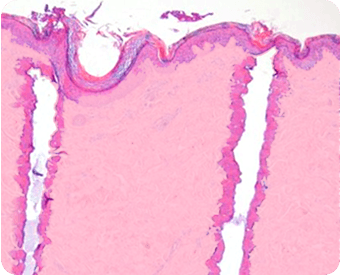

CO2 лазер испускает лазерный луч с длиной волны 10 600 нм, поглощаемый водой, содержащейся в тканях. Энергия лазера разогревает воду до состояния кипения, вызывая вапоризацию пораженной ткани. Какое-то количество тепла поглощается окружающими тканями, вызывая коагуляцию, приводящую к гемостазу (остановке кровопотери), а также термическую стимуляцию глубоких слоев кожи, активизирующую фибробласты и приводящую к неоколлагенезу (формированию нового коллагена).

Лазерный луч может также доставляться через сканер, используемый для контроля доставки энергии. Сканер регулирует способ доставки энергии, который может приводить как к сплошному покрытию зоны лечения, так и к фракционному (оставляя интактными участки между зонами повреждения); (так же известно как фракционная абляция).

Общий эффект абляции и коагуляции, полной или фракционной, заключается в удалении пораженной кожи и стимуляции организма замещать эти участки новой молодой кожей.